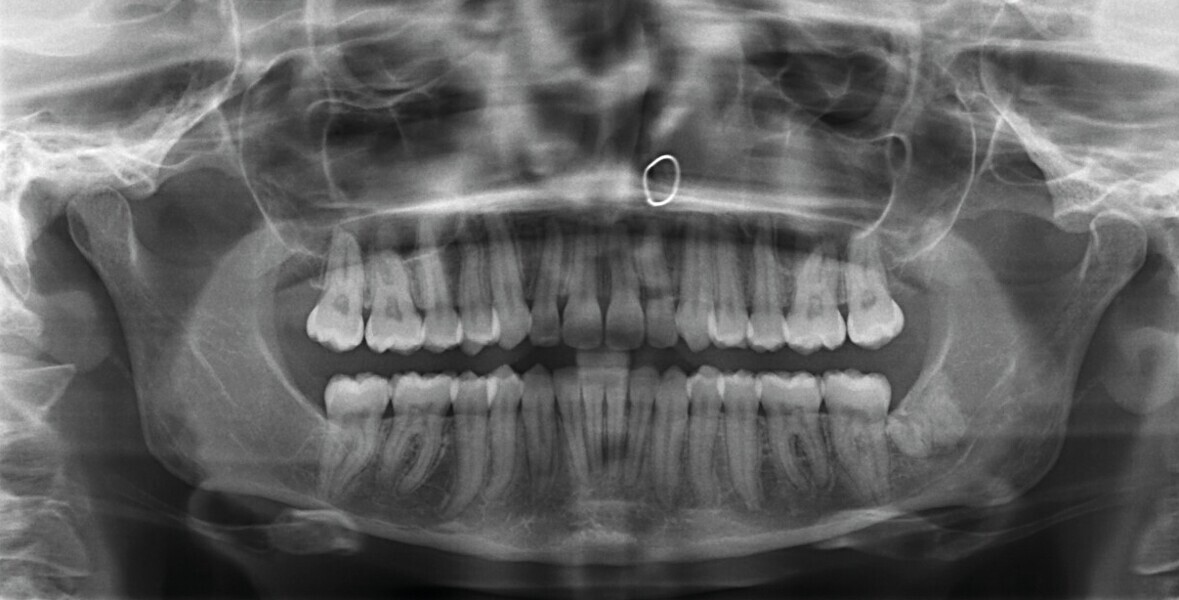

Fig. 2 : Radiographie panoramique initiale.

L’analyse radiographique indique une structure et une morphologie normales des racines. Un vestige radiculaire est encore présent dans la zone de la dent 38 qui a été extraite (Fig. 2). L’analyse céphalométrique montre un schéma squelettique de classe I avec vestibulo-version légèrement marquée des incisives maxillaires et mandibulaires (Fig. 3).